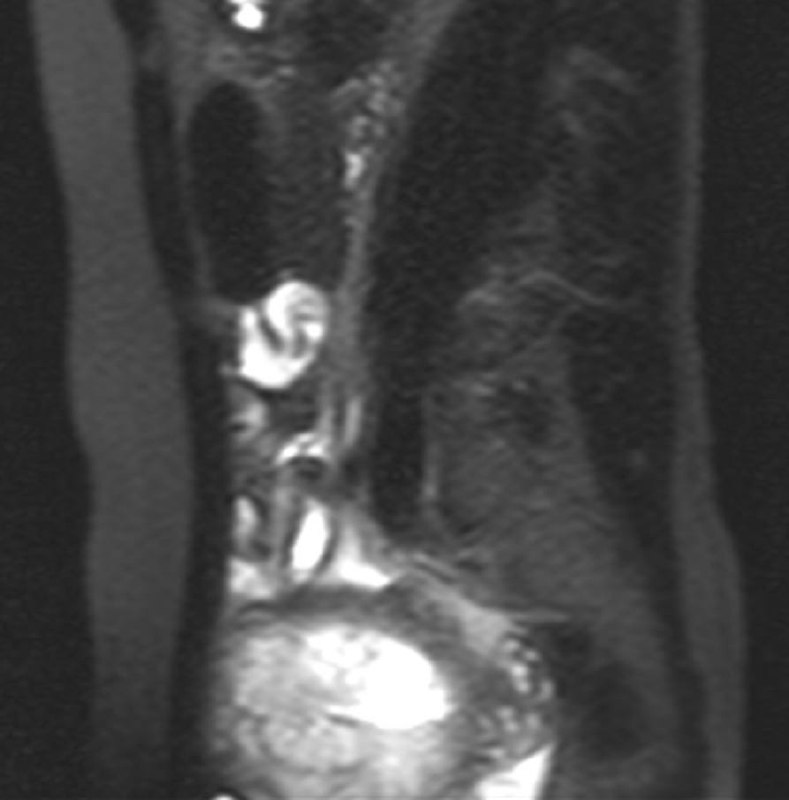

Одно из самых паскудных проявлений злокачественной опухоли - перитонеальный карциноматоз.

Средняя выживаемость при нем по одним данным составляет от 2,3 до 9 месяцев, по другим - варьирует от 11 до 17 месяцев при первичной опухоли, и зависит от стадии первичной опухоли при вторичном (стадии 0-2 - 5-10 месяцев, стадии 3-4 - 2-3,9 месяцев). Расположение первичной опухоли также может влиять на показатели выживаемости: при колоректальной карциноме средняя продолжительность жизни составляет 6,9 месяцев. Средняя продолжительность жизни при опухоли желудка составляет 6,5 месяцев.

Девушка 72 лет с карциноматозом брюшины, известно, что была гистерэктомия, а при перитонеальном карциноматозе, вызванном раком эндометрия средняя продолжительность жизни не превышает 12 месяцев, хотя при проведении циторедуктивной хирургии в сочетании с гипертермической внутрибрюшинной терапии описывают случаи продолжительности жизни и до 3 лет (интересно, что саудиты такое опубликовали, можно ли верить? Хотя, французы опубликовали, что после такого лечения аж трое пациентов прожили 7, 23 и 39 месяцев).

А у вас в местечке проводят такую терапию?